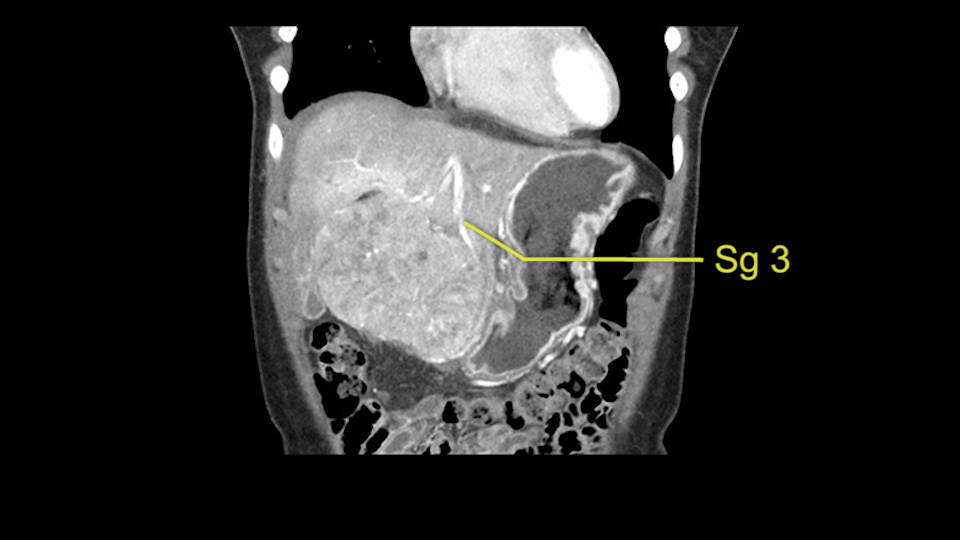

As I review the CT scan, we have both arterial and venous phases, the tumor is obvious. But I’ll start by saying that the liver itself does not appear to be cirrhotic to my eye. It’s got a normal contour and allied to that, that I do not see evidence of portal hypertension. The spleen is normal, there’s no collateral vessels. The tumor itself, I measured maximally at about 11 centimetres in diameter and I’m told the alpha fetoprotein is very high (over 10000), which is entirely consistent with this being a solitary hepatocellular carcinoma that is very exophytic. It seems to emanate off the inferior margin of Segment 3 (because that’s the falciform). I’ll start by saying that this is not transplantable. The tumor exceeds our guidelines for transplantation, but it's likely resectable based on normal liver and no portal hypertension.

So the issue with regards to resection. A left sided tumor. I believe I can see the falciform ligament right here so we’re looking at a resection of Segments 2, 3 of the left lobe of the liver. The left portal vein is right there. I think we’ll be wiser to take the left portal vein and therefore get well into Segment 4 and do a left hemihepatectomy. Certainly, one does not need to take the middle hepatic vein; it’s miles from the tumor.

The other thing I would do in this case is to certainly to assess the coronal phase as we can see in the coronal phase, this tumor looks like it's growing from Segment 3, and again I don’t think there’s involvement of the right side of the liver or even on Segment 4.